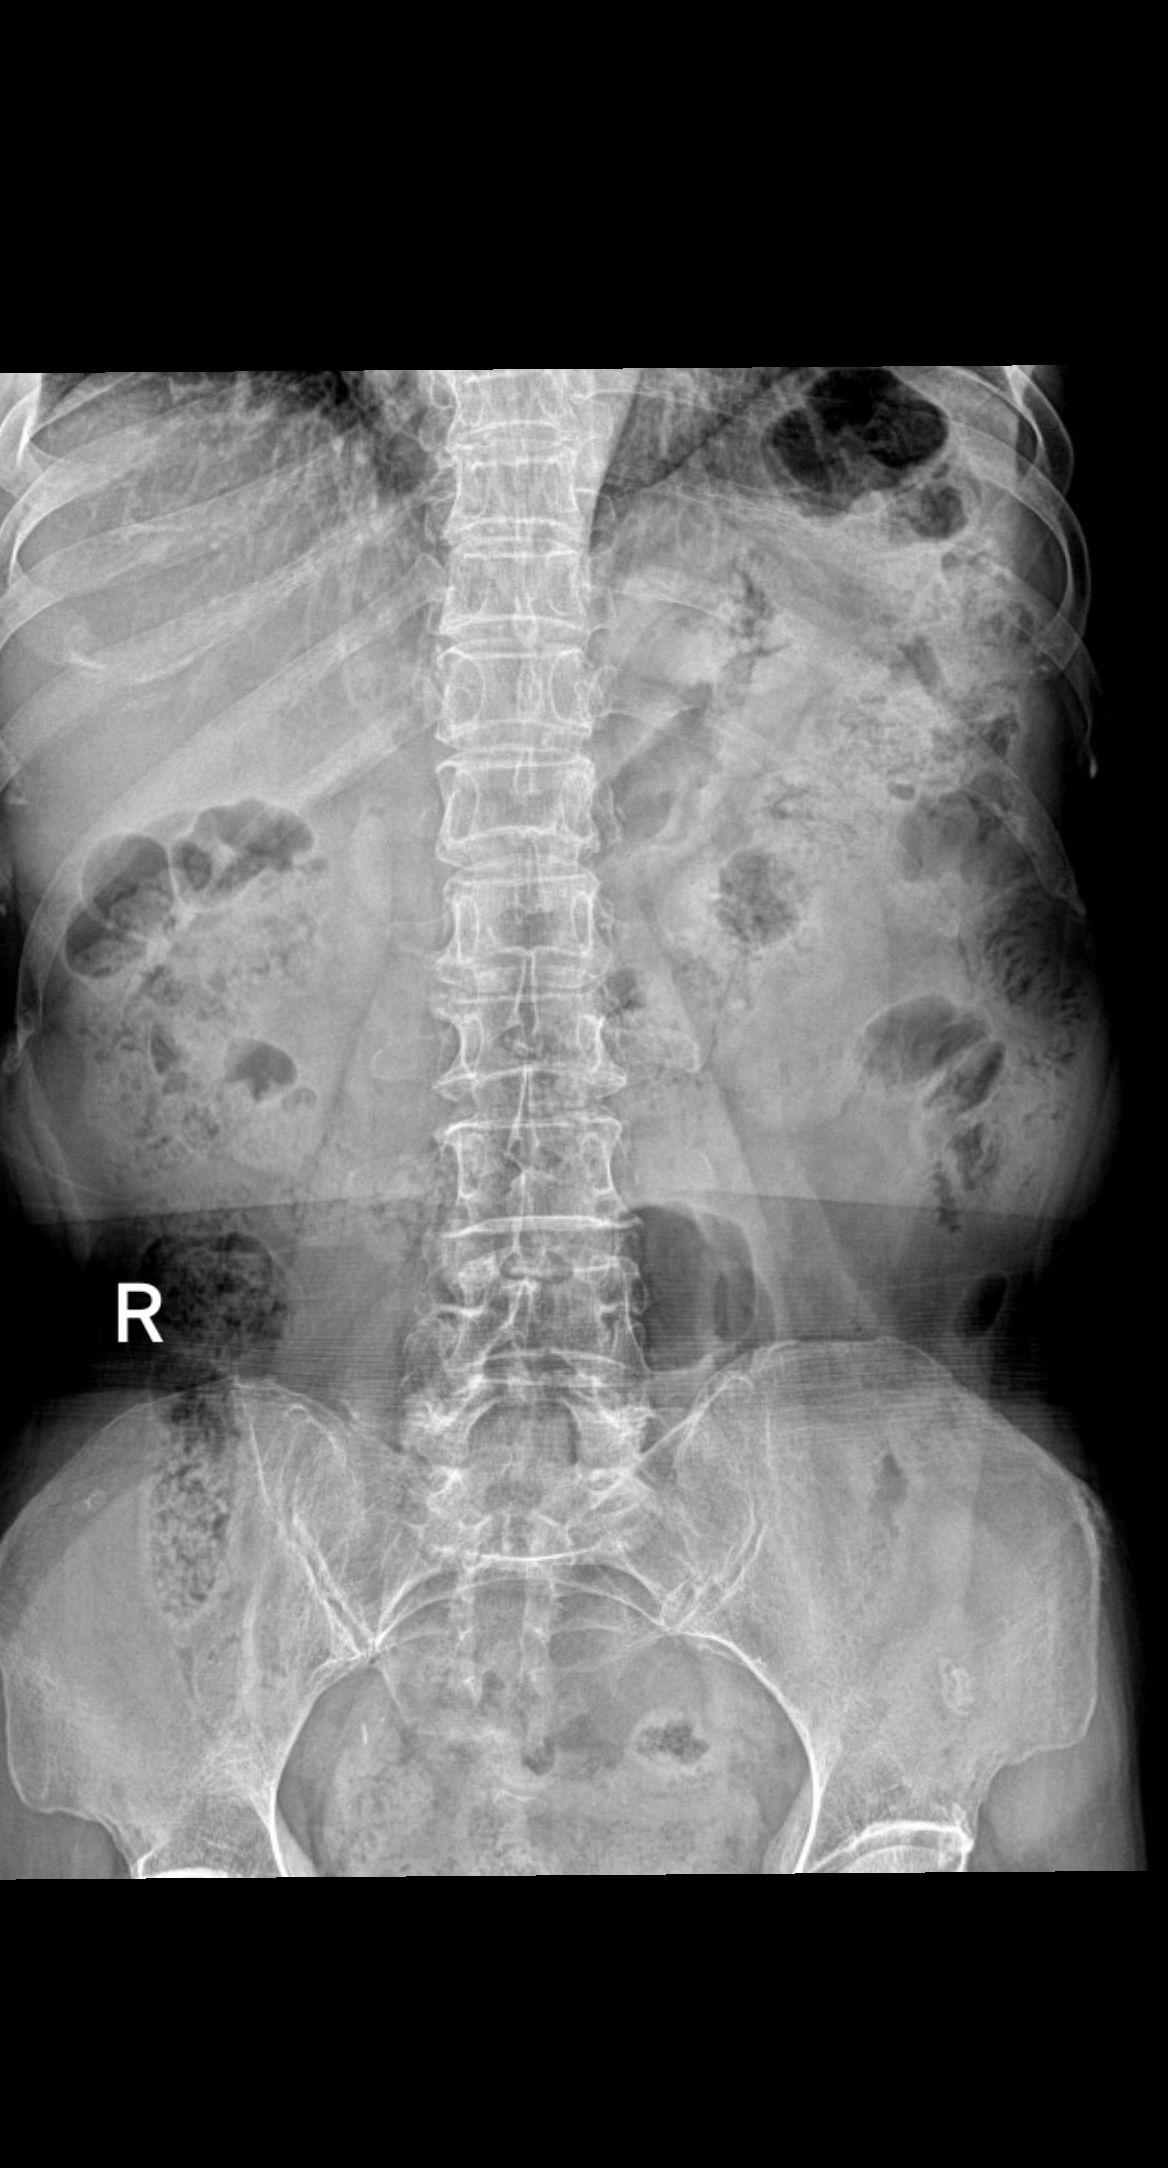

男,79y,腰疼就诊